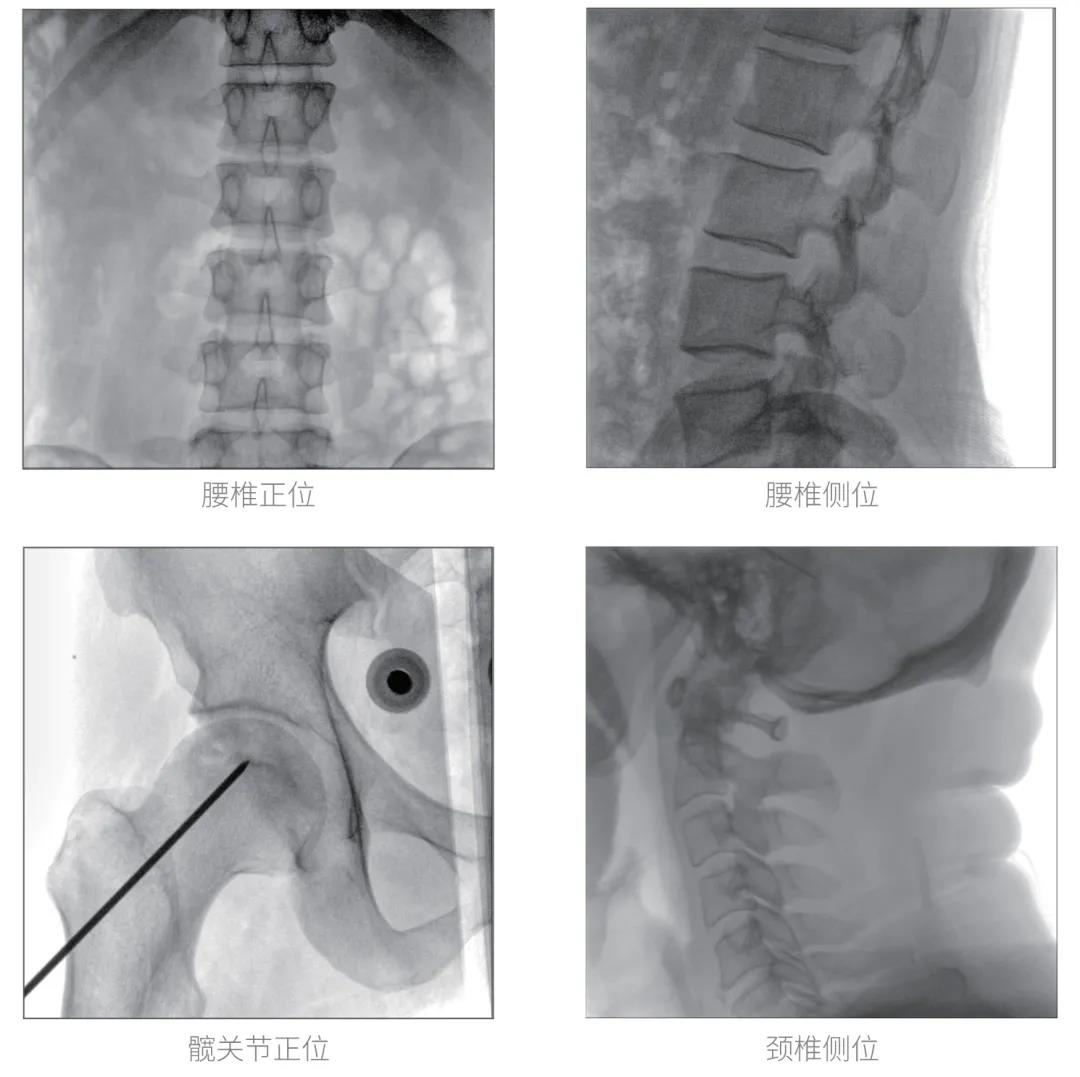

經過認真詳盡的設備審核驗收,“慧瞳”正式投入使用,普愛醫療一體化平板C形臂采取的動態平板探測器和智能圖像處理技術,讓臨床圖像更加清晰。

普愛醫療一體化平板C形臂“慧瞳”采用小巧緊湊的一體化機架設計,配合高性能的動態平板探測器,移動靈活,成像清晰,是各級醫院開展骨科及其相關外科手術的科室使用的理想設備。

智能化實時圖像處理技術,自動分析圖像并進行增強處理,減少臨床應用中處理圖像時的繁瑣操作,快速提供優質圖像方便完成臨床工作。